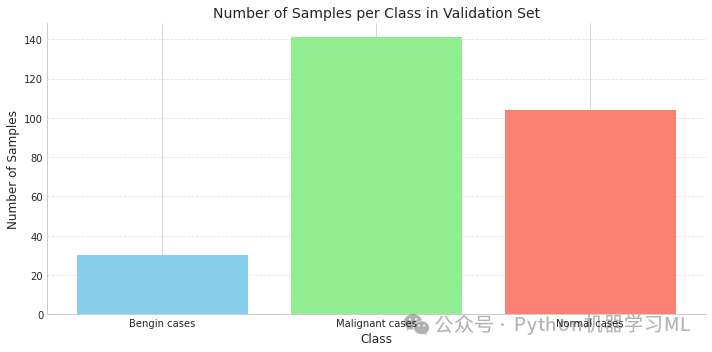

第四阶段**:类别不平衡可视化**

python# 4. Class imbalance visualization

plt.figure(figsize=(10, 5)) # 创建图形

class_counts = np.bincount(y_valid) # 计算验证集中每个类别的样本数量

plt.bar(range(len(categories)), class_counts, color=['skyblue', 'lightgreen', 'salmon']) # 绘制柱状图

plt.xticks(range(len(categories)), categories) # 设置x轴刻度标签

plt.title('Number of Samples per Class in Validation Set') # 设置标题

plt.xlabel('Class') # 设置x轴标签

plt.ylabel('Number of Samples') # 设置y轴标签

plt.grid(True, linestyle='--', alpha=0.6, axis='y') # 添加y轴网格

plt.tight_layout() # 调整布局

plt.show() # 显示图形